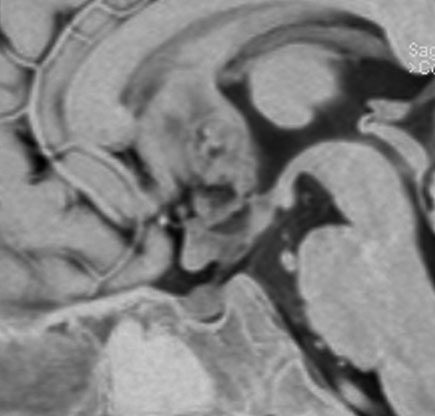

8歳で身長の伸びが悪くなり3年間診断されませんでした。12歳時に軽度の尿崩症を併発して発見されたものです。下垂体前葉機能はGH不全の他にはありません。

非常に典型的な下垂体後葉germinomaの画像です。萎縮して残った前葉線組織が前方にありガドリニウム増強されます。薄く増強されているトルコ鞍背部がgerminomaです。経蝶形骨洞手術で下垂体底面をもちあげて生検を行いました。

CBDCA/VP-16 3コースの後で,全脳室照射25.2Gy/14frを加えて治癒しています。成長ホルモンで身長も伸びて,11年が経過し,社会人として普通に暮らせています。